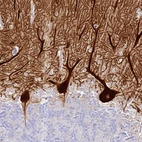

Immunohistochemistry analysis in human spleen and pancreas tissues using HPA040999 antibody. Corresponding HOMER3 RNA-seq data are presented for the same tissues.